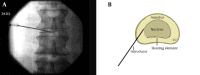

Figure 23.

Figure 23.. A and B, Biacuplasty® Procedure With Cooled Radiofrequency

The entry point is at the posterolateral annulus and the thermal element is guided through the introducer at the annular-nuclear junction with the final position in the posterior aspect of the disc.